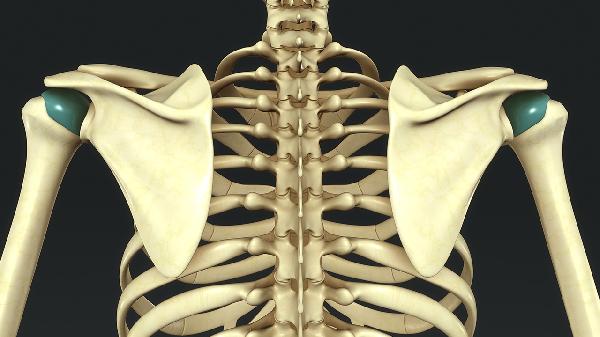

鼻窦骨瘤可能起源于胚胎期软骨内成骨过程中的细胞残留,这些异常分化的成骨细胞在鼻窦黏膜下持续增殖。此类骨瘤多见于筛窦和额窦,常与颅面骨发育畸形共存,影像学可见边界清晰的致密骨性结构。